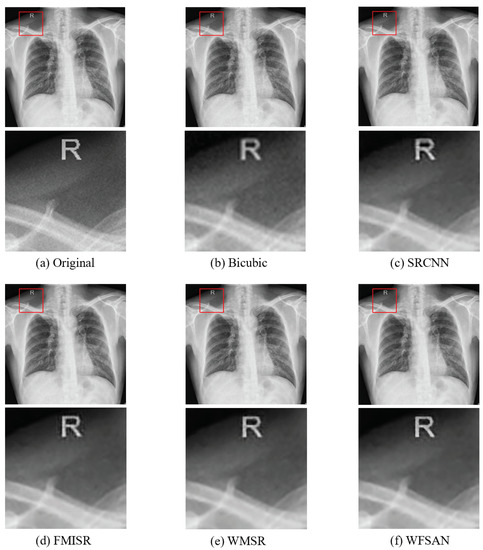

4.2. Quantitative Results

4.4. Discussion